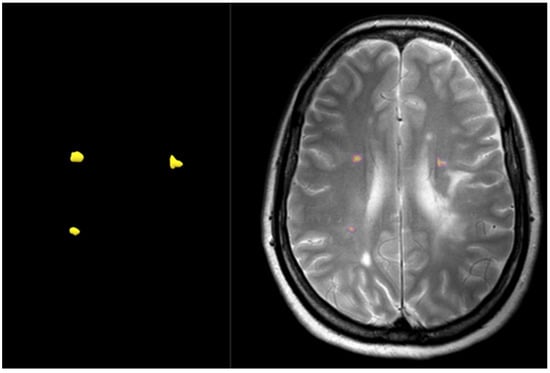

3.1.2. MRI Acquisition

3.1.3. MS vs. NMO Diagnosis